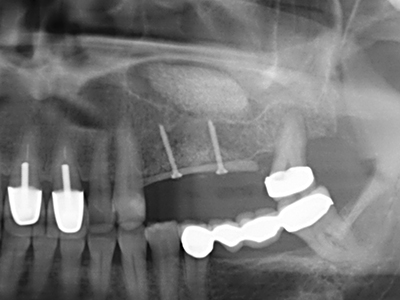

En la extracción de bloques óseos la piezocirugía también presenta ventajas adicionales: Además de la alta precisión en la osteotomía que ya se ha descrito antes, se ha comprobado que el uso de los delgados insertos de sierra resulta especialmente cuidadosas con el hueso. Frente a esto, sobre todo cuando se usan las fresas de Lindemann, cabe esperar pérdidas en la extracción significativamente más altas debido al mayor grosor de la parte frontal del cabezal (Lakshmiganthan, Gokulanathan et al. 2012). La separación basal que se necesita en particular en los injertos de bloque extraídos de forma retromolar se ve facilitada mediante sierras perpendiculares especialmente previstas a tal fin, lo que permite considerar que la cirugía piezoeléctrica es un procedimiento preciso y seguro para la obtención de bloques de hueso en el área retromolar (Happe 2007) (fig. 1-12).